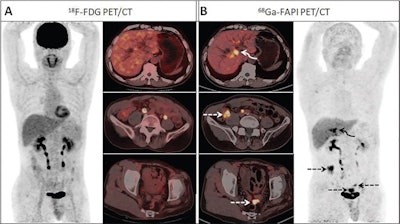

Images from a 59-year-old man who presented with yellow discoloration and pruritus of the skin for three months. A liver function test revealed increased bilirubin. (A) F-18 FDG-PET/CT images demonstrate no abnormal uptake throughout the abdomen, although the corresponding CT scan shows intrahepatic bile duct dilatation. (B) Ga-68 FAPI-PET/CT revealed increased uptake in the perihilar bile duct (SUVmax, 8.2). Three areas of intensive uptake were also observed on the thickening mesentery in the right lower abdomen and pelvic cavity (dashed arrows; SUVmax, 8.6). Slightly elevated Ga-68 FAPI uptake was observed around the dilated intrahepatic bile duct, suggesting cholangitis secondary to obstructive perihilar bile duct carcinoma. Mesentery tissue sample biopsy revealed metastatic adenocarcinoma from biliary cancer. Image courtesy of Radiology.Ga-68-labeled FAPI is an experimental radiotracer that binds to fibroblast proteins on the surface of cancer cells, thus revealing tumors on PET imaging. In the past few years, FAPI-PET has emerged as a promising approach with high tracer uptake in a variety of cancers.